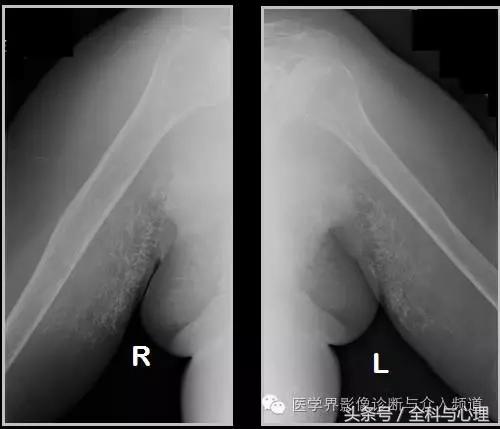

六、肌腱钙化/滑囊炎并钙化

肩关节最常见:肱二头肌长头、肩峰下滑囊钙化,可伴有急性疼痛、肿胀,局部压痛。

肱二头肌肌腱钙化(肩周炎)

肩周炎